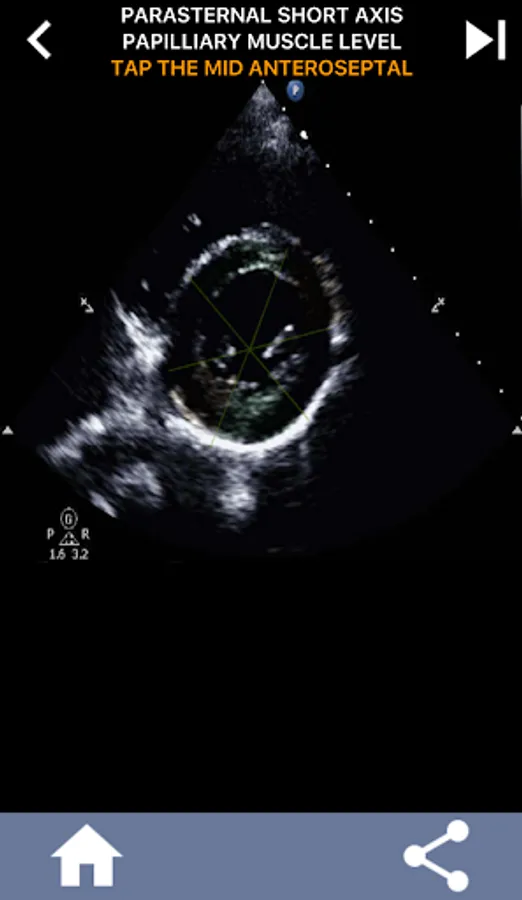

This app will test your knowlegde using actual echo images, which I often find to be the best teaching method.